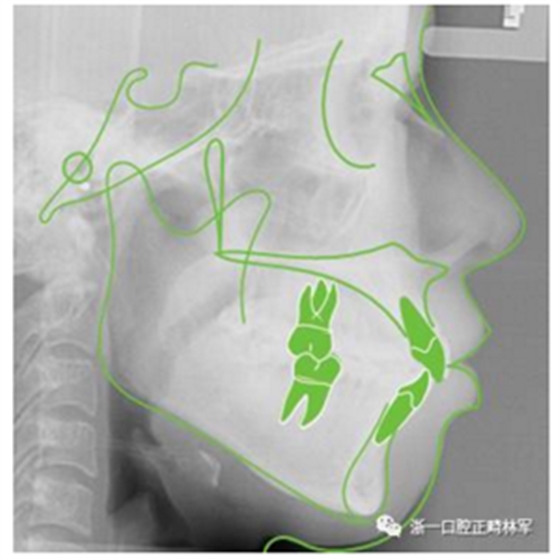

治療前側(cè)位片

頭影測量分析

Ricketts分析

Andrews六要素分析